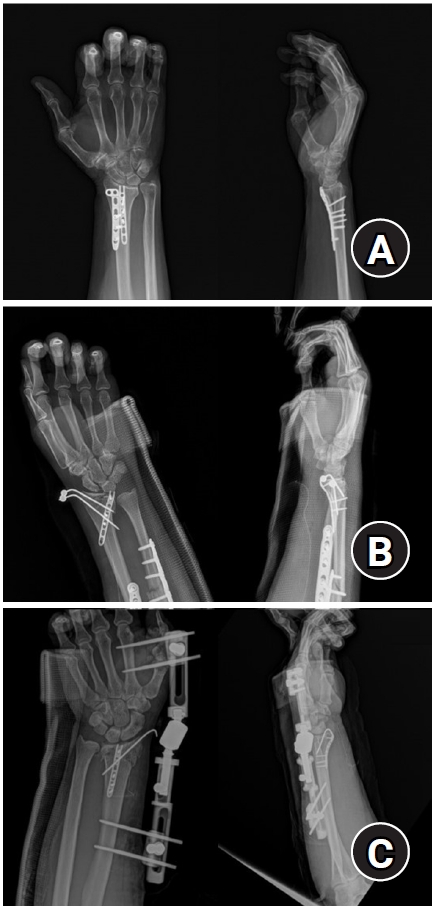

Fig. 2.

Postoperative radiographs (A) anteroposterior and (B) lateral: a 2.0 mm locking compression plate distal ulnar hook plate (Synthes) used for fixation in a distal radius fracture with a volar lunate facet fragment.

jmt-2025-00241f2.jpg

Fig. 2. Postoperative radiographs (A) anteroposterior and (B) lateral: a 2.0 mm locking compression plate distal ulnar hook plate (Synthes) used for fixation in a distal radius fracture with a volar lunate facet fragment.